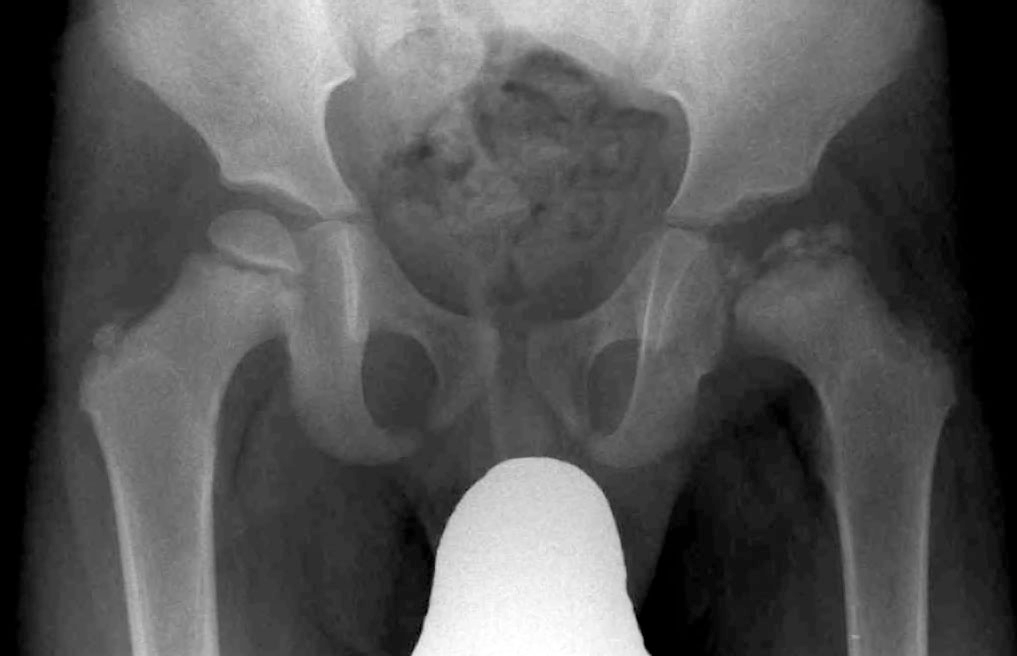

A hereditary condition in which failure of the resorptive mechanism of calcified cartilage interferes with its normal replacement by mature bone. Results in a symmetric, generalized increase in bone density

Osteopetrosis (Marble Bone)